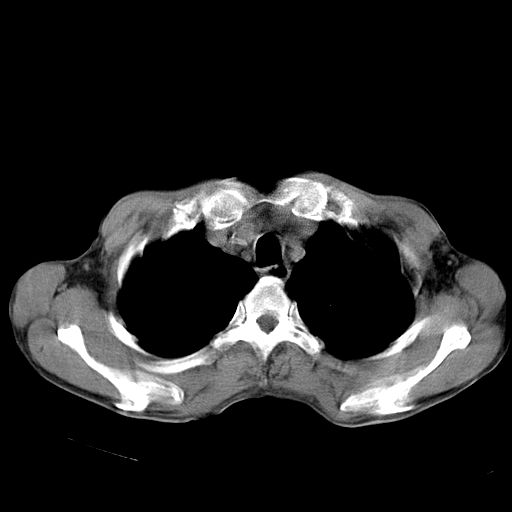

以下是引用苯小孩在2007-5-24 12:47:00的发言:[br]右侧肺门处不均匀密度软组织块影,远端肺组织见斑片模糊影,纵隔内淋巴结明显肿大,边界不清.<纵隔窗第12层面支气管内似见软组织结节>[br]考虑:1、右侧中央性肺癌并阻塞性肺炎并纵隔淋巴结转移可能性大.建议强化或纤支镜进一步检查.[br]2、隆突下淋巴结肿大/食道病变?请做鉴别检查.

以下是引用zhangzhongshou在2007-5-24 12:55:00的发言:[br]1、右肺中叶中心型肺癌并右肺门、隆突下、纵隔淋巴结转移。右肺中叶阻塞性肺炎。

以下是引用jw-830在2007-5-24 15:24:00的发言:[br][br] [br] 考虑右肺中央型肺癌并阻塞性炎症,右肺门及纵隔淋巴结转移。 [br] [br][br]